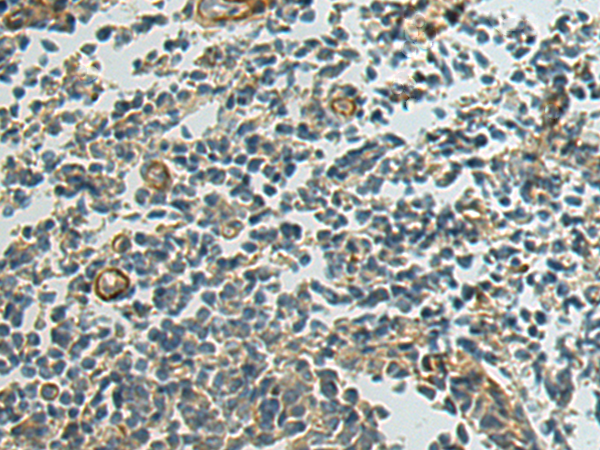

分类: 科研抗体货号: P04599别名: APG4B; AUTL1应用: IHC反应种属: Human